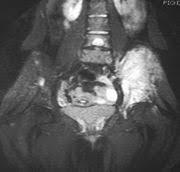

Boston College LB Herzlich diagnosed with cancerHerzlich said Thursday he was diagnosed earlier this week with Ewing's Sarcoma after feeling pain in his leg and will undergo more tests in his home state ... read more

AP Photo/Michael Dwyer Mark Herzlich said Thursday he has Ewing's Sarcoma, a cancer most often found in bone or soft tissue. ... read more

Kieran suffers from a rare form of bone cancer called Ewings Sarcoma, and since diagnosis last October has been attending hospital in Newcastle for ... read more